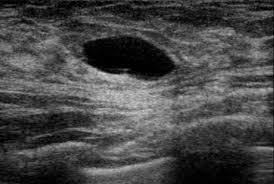

What Does Inflammatory Breast Cancer Look Like On Ultrasound - Plos One Incidence Of Inflammatory Breast Cancer In Patients With Clinical Inflammatory Breast Symptoms : Inflammatory breast cancer is an uncommon form of breast cancer but is very aggressive.. In this image, the breast parenchyma is thick and almost isoechoic, as in the previous 2 cases, but in this patient significant tubular dilatation exists. Your outlook depends on many things, like your overall health, the. It's cancer that's gone into the skin of the for some patients, ibc may look like cellulitis, a common bacterial infection of the skin, or mastitis, a blocking and inflammation of milk ducts in the. Like any other cancer, breast cancer can be divided into stages depending on how much the cancer has spread. It is referred to as inflammatory due to its frequent presentation with symptoms resembling a skin inflammation, such as erysipelas.

What is inflammatory breast cancer (ibc)? Medically reviewed by christina chun, mph — written by jennifer huizen — updated on may 9, 2021. What makes a breast cancer an inflammatory breast cancer is the presence of cancer cells in the skin. How does a radiologist see breast cancer on mammography ? Your outlook depends on many things, like your overall health, the. Inflammatory breast cancer is an uncommon form of breast cancer but is very aggressive. Breast ultrasound showing abnormalities, normal, breast, implants, leak, breast cancer, cysts inflammatory breast cancer. Like ductal carcinoma, these typically metastasize to axillary lymph nodes first. The appearance of normal breast tissue on a mammogram. Mammographic and ultrasound features of inflammatory breast cancer. Can ultrasound detect breast cancer? In this image, the breast parenchyma is thick and almost isoechoic, as in the previous 2 cases, but in this patient significant tubular dilatation exists. This makes it harder to diagnose.